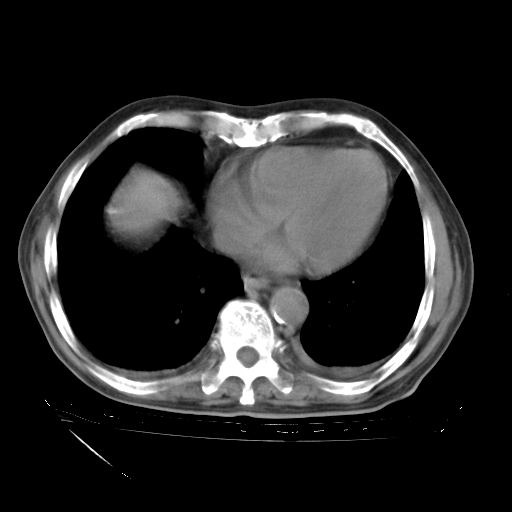

补充下:5月9日胸部CT:似乎已见双下肺胸腔积液了,鉴于目前有下肢水肿,肝功示:白蛋白低,应注意多浆膜腔积液(漏出液可能大?),需注意!

甲强龙80mg/日+抗结核治疗(异烟肼+利福霉素+乙胺丁醇)10天。复查肺部CT。

治疗10天肺部CT